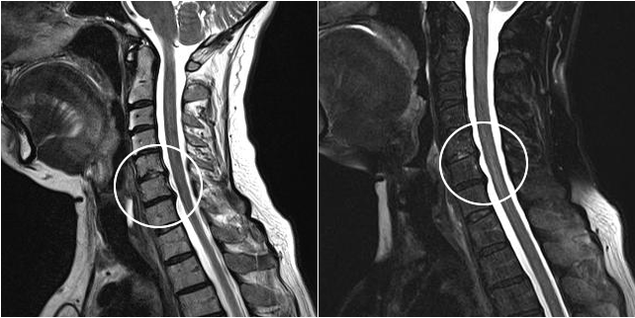

Modern diagnostic methods include MRI and CT, which make it possible to most accurately study the processes of destruction of cartilage and bone tissue.This technique can also be used to conveniently diagnose hernias and other soft tissue defects near the source of the disease.